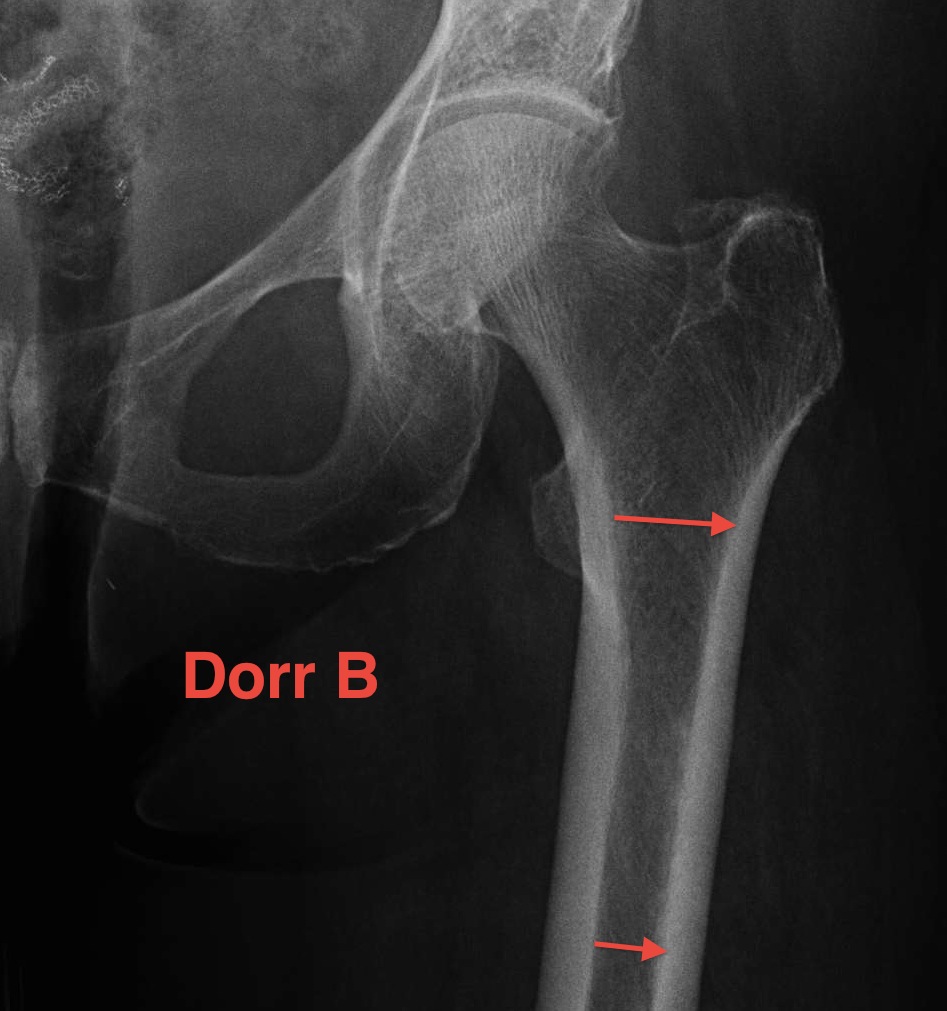

Dorr Classification of Proximal Femoral Geometry

Technique

- measure intra-medullary canal at lesser trochanter & 10cm below

- diameter 10 cm distal divided by inner diameter at midportion of lesser trochanter

- must be <75% for uncemented prosthesis

| Type A / Champagne Flute | Type B | Type C / Normal |

|---|---|---|

| Ratio < 0.5 | Ratio 0.5 - 0.75 | Ratio > 0.75 |

| Thick cortices | Wide canal diameter | |

| Young males | Elderly females | |

| Small diaphysis and thick cortex risks fracture | Cemented stem |